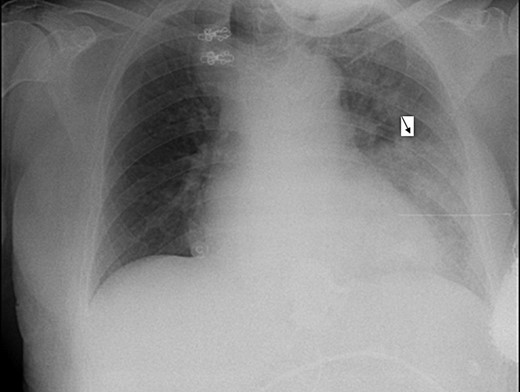

During her hospitalization, the patient developed fever and desaturation, with a new infiltrate on CXR (Fig. 3). She was diagnosed with pneumonia and was treated with antibiotics. Later on, after significant improvement, though still suffering from a barking cough (attributed to reflux), the patient left her bed and in an attack of severe coughing, lost consciousness, fell and became cyanotic. Repeated attempts to improve oxygenation failed until a naso-gastric tube was inserted with drainage of ∼1 l of non-bilious content, resulting in rapid improvement in the patient's condition. A repeat CXR revealed the naso-gastric tube in her esophagus. Repeated attempts to insert the NGT into her stomach failed, even with the aid of contrast media. The silastic band was then deflated, allowing for less restriction, and an endoscopy showed esophagitis but no obstruction.